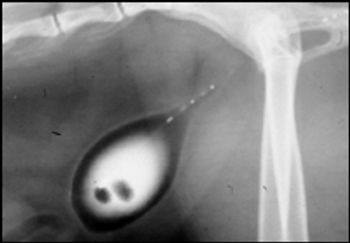

Results of experimental and clinical investigation have confirmed the importance of dietary modifications in medical protocols designed to promote dissolution and prevention of uroliths.